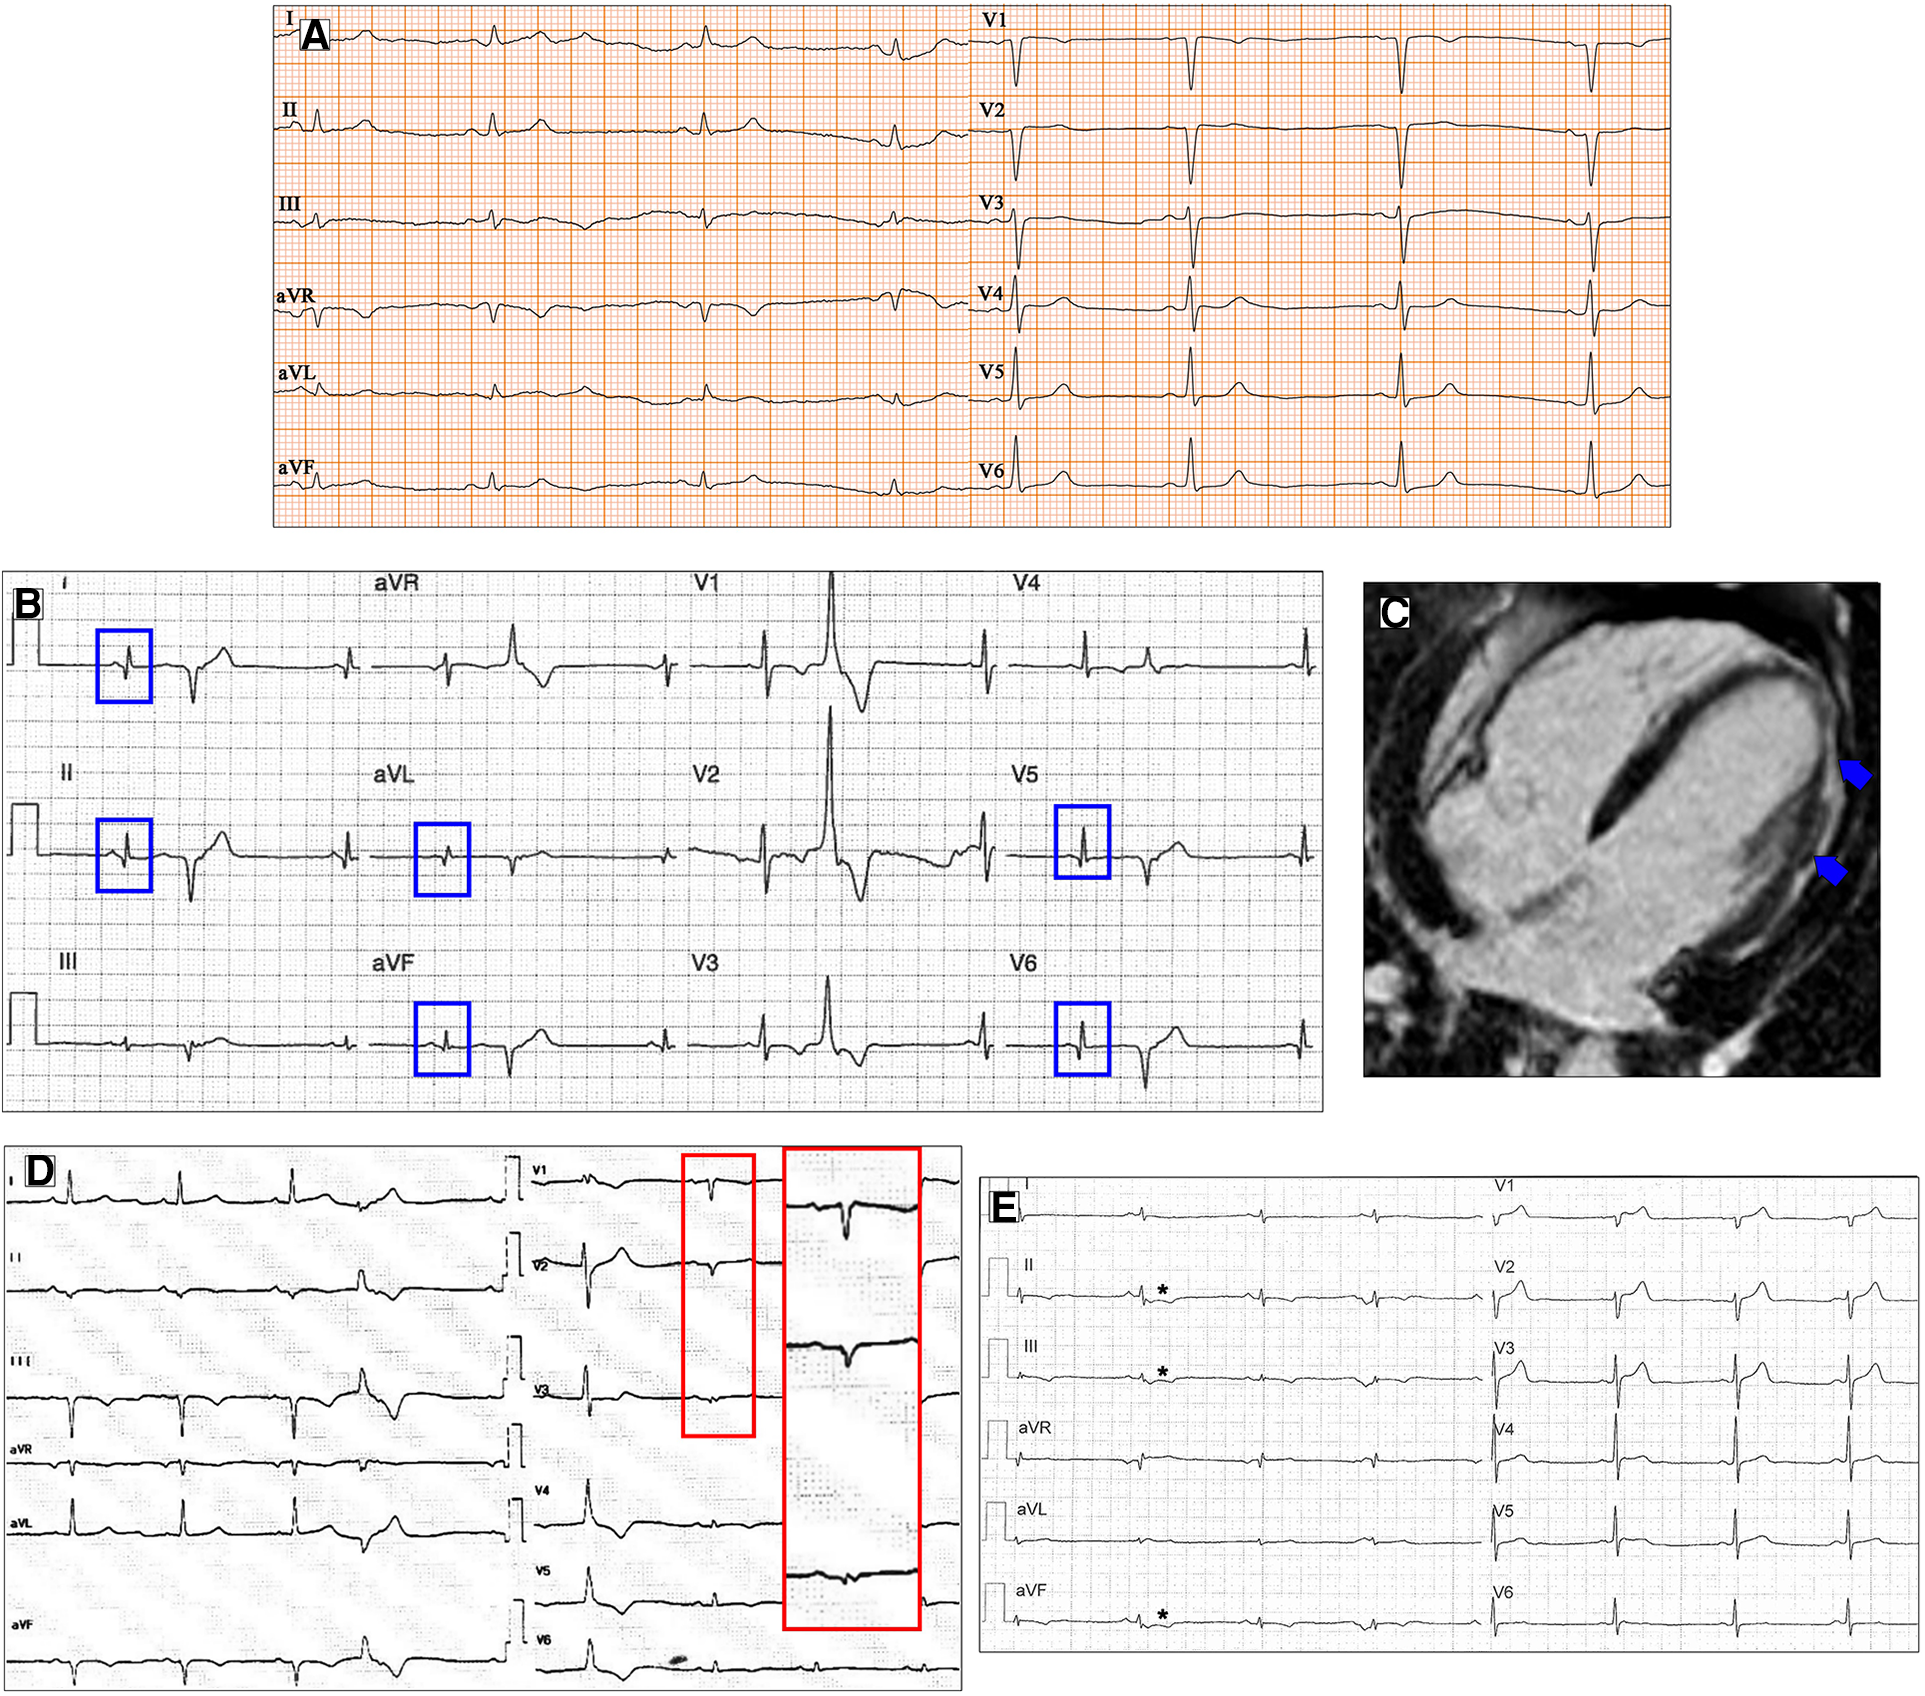

Figure 1

Conduction disorders in patients with DCM. ECG performed in a 60-year-old man with DCM shows LBBB and normal QRS axis (A). Basal ECG of a 78-year-old patient fulfills criteria for LAFB (B). ECG and CMR findings of a 20-year-old male with history of ventricular arrhythmias and mild LV dysfunction. Basal ECG (C) showing low QRS voltages (<0.5 mV) in limb leads and LPFB (AQRS ≈ + 110°). Post-contrast image showing subepicardial circumferential LGE pattern (D). Four-chamber CMR image of a 42-year-old man presented with pulmonary edema showing severe LV dilation (E). ECG at presentation displaying normal QRS axis, intraventricular conduction delay, signs of LVH (Sokolow–Lyon criteria) with secondary repolarization abnormalities (F). All the ECGs presented in the figure were performed at 25 mm/s with 1 mm/mV. ECG, electrocardiogram; CMR, cardiac magnetic resonance; DCM, dilated cardiomyopathy; LAFB, left anterior fascicular block; LBBB, left bundle branch block; LGE, late gadolinium enhancement; LPFB, left posterior fascicular block; LVH, left ventricular hypertrophy.

In addition, left anterior fascicular block and non-specific intraventricular conduction delay, while not being specific ECG signs, have also been found in a small percentage of DCM patients (12) (Figure 1B). Left posterior fascicular block (LPFB), which is uncommon in the general population, has been associated in a recent small study with extensive LV scarring and an increased risk of sudden death (18) (Figure 1C,D).

Regarding LVH, the literature describes a presence ranging from 17% to 69% according to the Sokolow criteria (12) (Figure 1E,F). In DCM patients with LVH voltage criteria (6), a hypertensive etiology should be excluded. Interestingly, in a retrospective study by Merlo et al. (14), LVH showed a protective role, probably expressing a prognostic benefit due to an increased left ventricular mass.

Figure 2

Ventricular depolarization and repolarization abnormalities in patients with DCM. A 30-year-old female with a likely pathogenic variant in FLNC gene. Twelve-lead ECG shows low QRS voltages both in limb and precordial leads (A). Basal ECG of a 46-year-old patient with DCM showing pathological infero-lateral Q waves (blue boxes, B); a premature ventricular beat with RBBB morphology and superior axis is also present. Post-contrast CMR images of patient in panel B showing subepicardial LGE involving the left ventricular lateral wall (blue arrows, C). A 38-year-old male with a pathogenic variant in LMNA gene and familiar history of DCM and sudden cardiac death. Basal ECG displaying low QRS voltages in precordial leads and specific ECG signs of “septal remodeling” (pathological Q waves, QRS fragmentation, poor R-wave progression in V1–V3 leads; red box); a premature ventricular beat with RBBB morphology and right axis deviation is also present (D). Basal ECG of a 39-year-old DSP mutation carrier shows low QRS voltages in limb leads, negative T waves in inferior leads (asterisks, E). All the ECGs presented in the figure were performed at 25 mm/s with 1 mm/mV. ECG, electrocardiogram; CMR, cardiac magnetic resonance; DCM, dilated cardiomyopathy; LGE, late gadolinium enhancement; RBBB, right bundle branch block.

Q waves have been described more frequently in anterior and lateral leads in DCM, despite normal coronary arteries (14) (Figure 2B,C). ECG signs of “septal remodeling,” such as pathological Q waves in leads V1–V2, have been described in Lamin A/C (LMNA) mutation carriers (28) (Figure 2D). The presence of a pseudoinfarction pattern in posterior, postero-lateral, and inferior leads should suggest dystrophin-related disease (29).